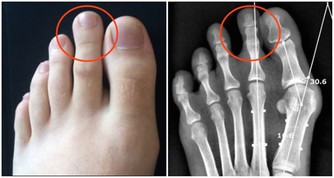

為什麼會長痘? 痘痘的產生有內因和外因兩種原因。中醫認為,皮膚是機體外表的一部分,它與臟腑、經絡、氣血等有著密切的關係。各種內外在因素作用於人體,引發臟腑功能失常,它表現在肌膚上,就會產生痘痘。由此可知:其中,內分泌失調及其引發的臟腑功能失常是引起痘痘的根本原因,不良生活習慣等是痘痘產生的外因,因此祛痘應內外結合。 長痘內因:內分泌失調及其引發的臟腑功能失常(圖解:痘痘位置告訴你哪裡出了問題)